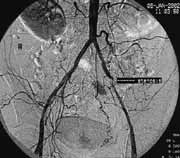

Рис. 2. Сегментарные стенозы подвздошных артерий, критический стеноз левой наружной подвздошной, окклюзия левой внутренней подвздошной артерий.